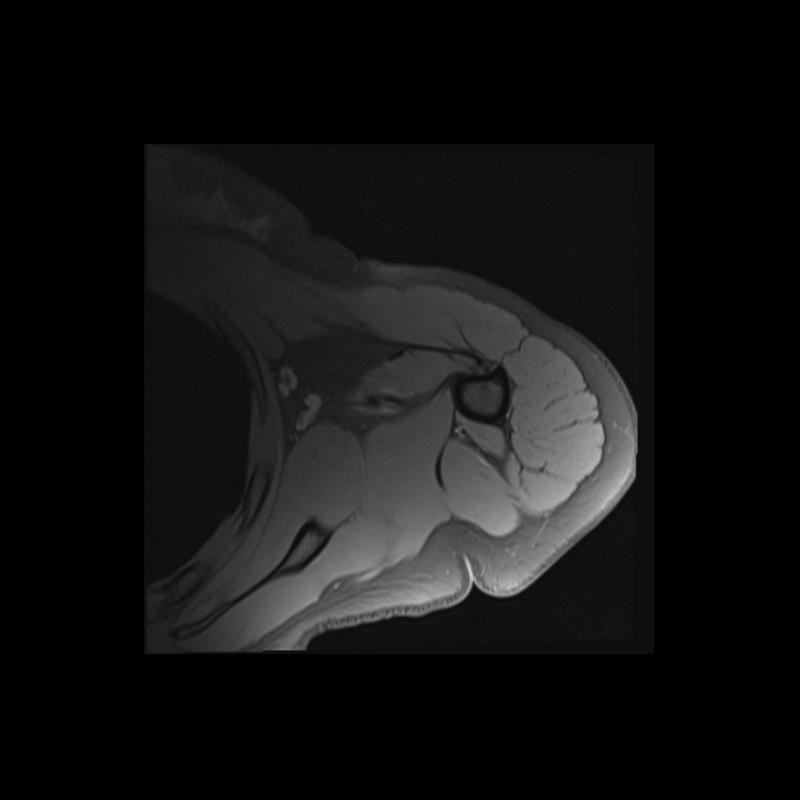

Shoulder MRI Anatomy